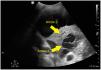

A 52-year-old patient with a history of acquired immunodeficiency syndrome (AIDS) was admitted to our Unit due to Streptococcus pneumoniae community-acquired pneumonia. The chest radiographs evidenced right basal infiltration, and the computed tomography (CT) study showed necrotizing pneumonia with a probable incipient lung abscess. The clinical course was poor, with hypoxemia refractory to cycles in prone decubitus. Pulmonary ultrasound revealed pleural effusion containing hyperechogenic fibrous tracts (plankton sign) (Fig. 1, arrow 1), right basal infiltration with hyperechogenic parenchyma secondary to hepatization, air bronchogram (Fig. 2, arrow 2), and well delimited internal hypoechogenic trabeculate zones consistent with necrotizing pneumonia and lung abscess (Fig. 2, arrow 3).